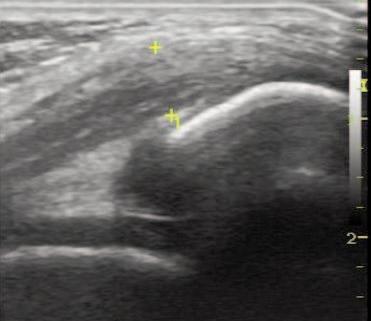

The Use of MSK Ultrasound with Quadriceps Muscle Injury.

Manske R, Voight M, Wolfe C, Page P.

Point of care ultrasound (POCUS), musculoskeletal ultrasound (MSK-US), and rehabilitation ultrasound imaging (RUSI) are similar procedures that use a non-ionizing imaging and is becoming more inexpensive, portable, safe, and able to be used quickly.1-4 These modalities are commonly used in various medical disciplines to assess musculoskeletal tissues (bones, muscles, tendons, ligaments, nerves) as well as structures such as the heart, lungs, and bladder just to name a few. MSK-US primarily focuses on the structural integrity or characteristics of the neuromuscular system. This would include viewing soft tissues for assessment of normalcy or abnormality. For example, viewing the supraspinatus for signs of swelling or a rotator cuff tear, or assessing the median nerve to measure swelling or size differences in those with carpal tunnel syndrome are commonly performed using MSK-US. RUSI is similar but includes the evaluation of muscle and soft tissue during exercise or movement dynamically including its use for biofeedback.5-6 An example of RUSI include realtime observation of spinal muscle (lumbar multifidus and transverse abdominus) activation patterns during exercise to facilitate improved neuromotor control.6